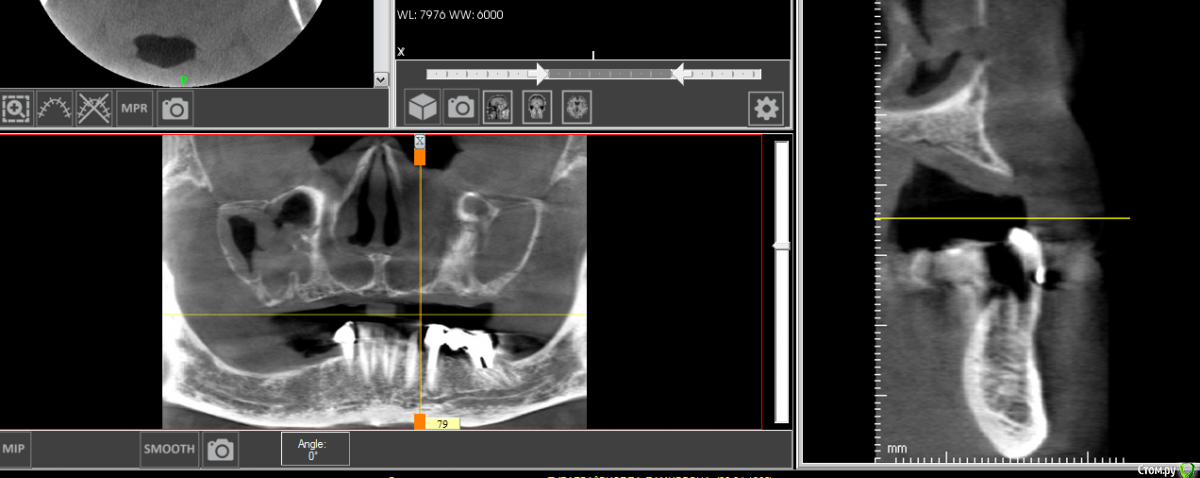

gum Опубликовано 3 декабря, 2020 Поделиться Опубликовано 3 декабря, 2020 Здравствуйте. Ситуация следующая: у 2 пациентов за последний год обнаружил продолжение нижнечелюстного нерва, ранее не сталкивался с таким. У одного во фронтальном отделе стояли имплантаты, через год началось отторжение, в апикальной части, сначала один, потом и второй.при повторной попытке установить имплантаты, анестезия действовала ровно полчаса, ставили в 2 этапа, первый день, разрез и ложе, во второй закрутил и зашил, зашивал уже с болями. Далее боли постоянные в течении 2 недель и сильные, итог все убрали, все прошло.Второй пациент при попытке установить имплантаты по месту 44,45 анестезия работает не более 20 минут, на этапе сверления боли, мандибулярную "постеснялся" делать после первого пациента.Оба пациента часто нервничают, в силу профессии.Вопрос как вести таких пациентов? Почему такая реакция, в 1 случае 6 имплантатов ставили без проблем, а с фронтальными сложности. Сможет ли невролог помочь? (На консультацию к нему направил).Кто сталкивался с подобным? Ссылка на комментарий

колесников Опубликовано 3 декабря, 2020 Поделиться Опубликовано 3 декабря, 2020 Интрасептальные ответвления n.alv. Защемление их приводит к таким последствиям. Внимательно смотреть клкт,тщательно планировать позиционирование импланта Ссылка на комментарий

shy Опубликовано 3 декабря, 2020 Поделиться Опубликовано 3 декабря, 2020 резцовые петли , 2 варианта в этой ситуации1)полностью спланировать позицию имплантата что бы обойти их2)полностью пересечь их , если 'недорезать' могут начаться боли в этой области и тут либо доставать имплантат либо ждать пока пройдет (а может и не пройдет)Невролог чем поможет? это анатомические особенности . Ссылка на комментарий

Александр07 Опубликовано 26 декабря, 2020 Поделиться Опубликовано 26 декабря, 2020 Согласен с тем что возможна психосоматика, и седация как вариант Как альтернатива помощь Невролога в плане подготовки Пац к операции- прием седативных препаратов курсом поможет снять стресс и напряжение как и с работой связанное так и с повторным вмешательством По срезам что скинули довольно глубоко расположен нерв и обойти должно получится Ссылка на комментарий